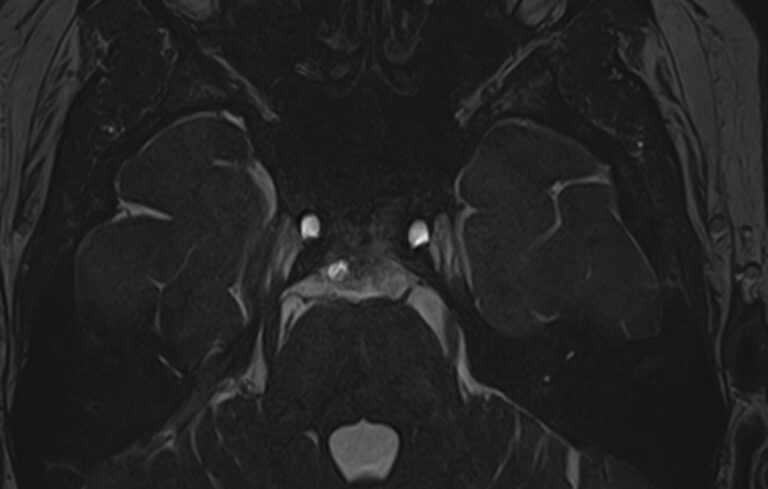

Для диагностики поражения черепно-мозговых нервов, а также оценки состояния окружающих их тканей и визуализации сосудистой сети головного мозга в клинике «Доступная медицина» проводится комплексное обследование МРТ головного мозга + Мр-ангиография головного мозга + МР-венография головного мозга + черепно-мозговые нервы. Данное обследование включает в себя несколько протоколов: стандартный – для оценки состояния всех структур головного мозга и дополнительные – для изучения очагов поражения черепных нервов и визуализации всей сосудистой системы головного мозга.

Исследования выполняются на современном высокопольном томографе экспертного класса TOSHIBA VANTAGE TITAN 1,5 Тесла, который использует разные режимы сканирования с толщиной среза от 1мм в различных плоскостях с последующей цифровой обработкой полученных данных для создания трехмерных изображений. МР-ангиография отображает состояние артериальной системы кровоснабжения головного мозга. МР-венография головного мозга позволяет детально изучить особенности венозного русла головного мозга.

Компьютерная программа обрабатывает данные, полученные при сканировании, и формирует объемные изображения как самого мозга, так и сосудистой системы в отдельности без прилегающих тканей. Методики применяются одновременно и взаимодополняют друг друга.

Данное комплексное исследование в большинстве случаев проводится с контрастным усилением, которое необходимо для улучшения визуализации черепно-мозговых нервов. Для этого внутривенно вводится препарат, содержащий гадодиамид (соли металла гадолиния) для получения изображений с высокой четкостью и контрастностью, что способствует ранней диагностике заболеваний головного мозга.